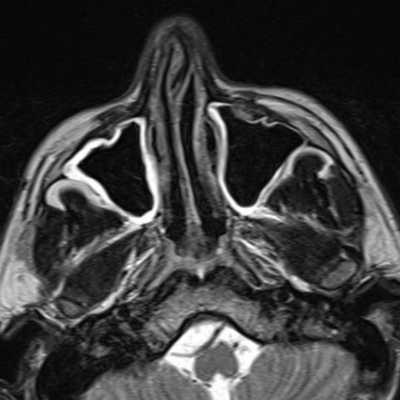

Магнитная томография околоносовых пазух: левосторонний сфеноидит